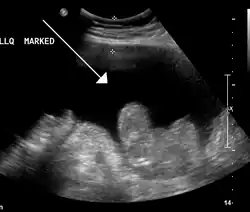

Ultrasound investigation is often done before attempts to remove fluid from the abdomen. This may reveal the size and shape of the abdominal organs, and Doppler studies may show the direction of flow in the portal vein, as well as detecting Budd–Chiari syndrome (thrombosis of the hepatic vein) and portal vein thrombosis. The sonographer also can estimate the amount of ascitic fluid, and difficult-to-drain ascites may be drained under ultrasound guidance. An abdominal CT scan is more accurate than a sonogram to reveal abdominal organ structure and morphology.[13]